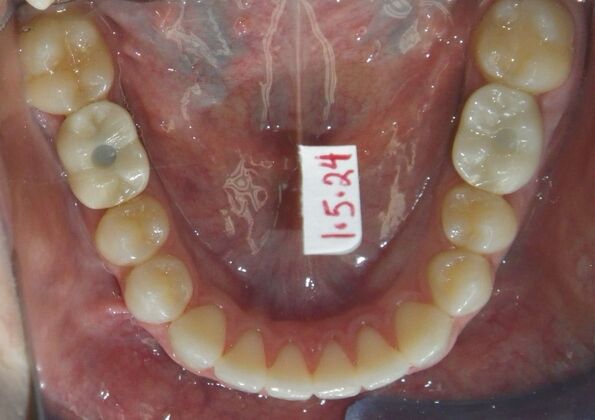

Invisalign: Case 17

This patient was an awesome dental assistant for our practice and we were all very sad when she had to move closer to her home. She was very interested in correcting some minor spacing and rotations in her upper and lower anterior teeth and to decrease her overbite as well.Treatment took about 12 months, but we were pleased with the results and fabricated clear invisalign vivera retainers. We are still hoping one day she will return to be with us again.